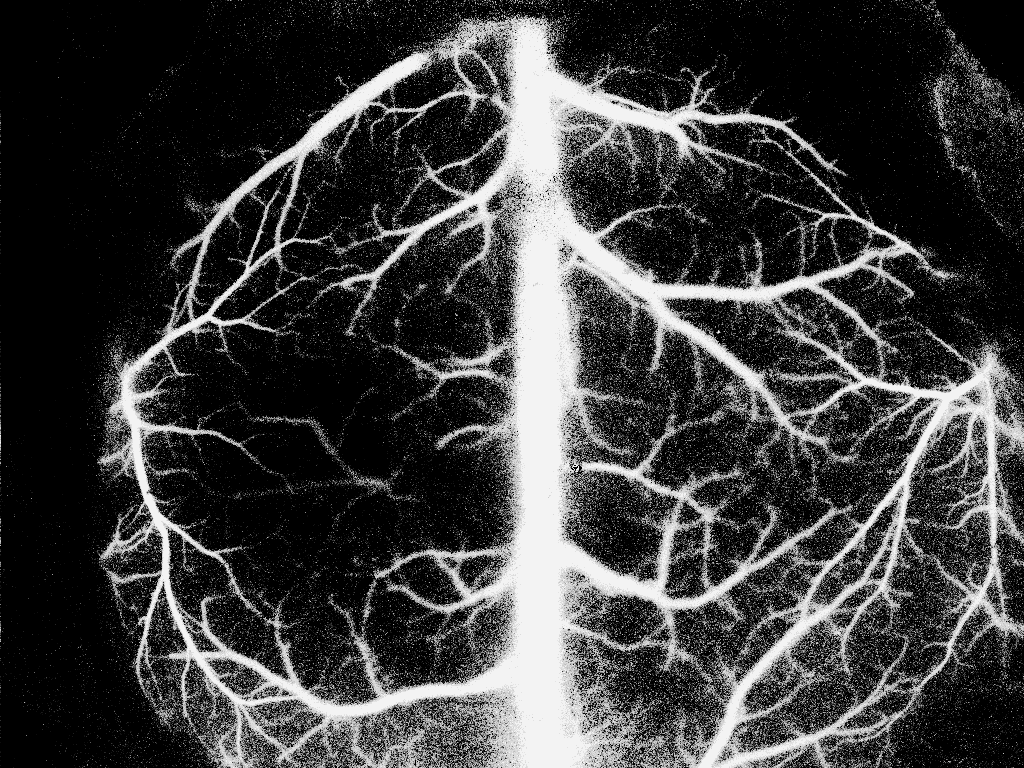

5. 上述直方图均衡算法还存在一个问题,就是当图像的0像素值占很大比例时,从起始的0像素值的累加概率就很大了,导致后面的1~255像素值的累加概率均变得很大,从而造成直方图均衡化之后的像素值都偏大。比如下图,可以看到直方图均衡化之后图像变白了,严重失真。

原图

直方图均衡化之后的图像